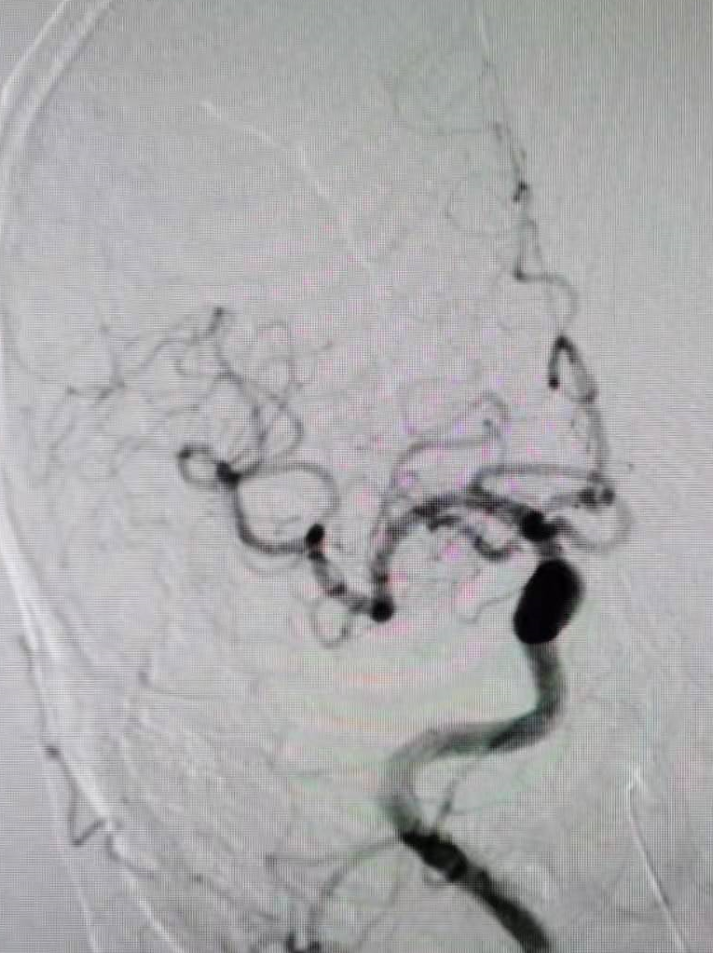

全脑血管造影提示右侧椎动脉颅内段闭塞,左侧椎动脉颅外段走形迂曲,基底动脉近端闭塞。

颈动脉造影示后交通开放。

扩张后造影,提示恢复正向血流,残余狭窄50%左右。发现加奇SacSpeed® 2.5mm×9mm颅内球囊扩张部位存在双腔征,考虑血管夹层,给予替罗非班8ml/h持续泵入。

观察5分钟后再通血管闭塞。